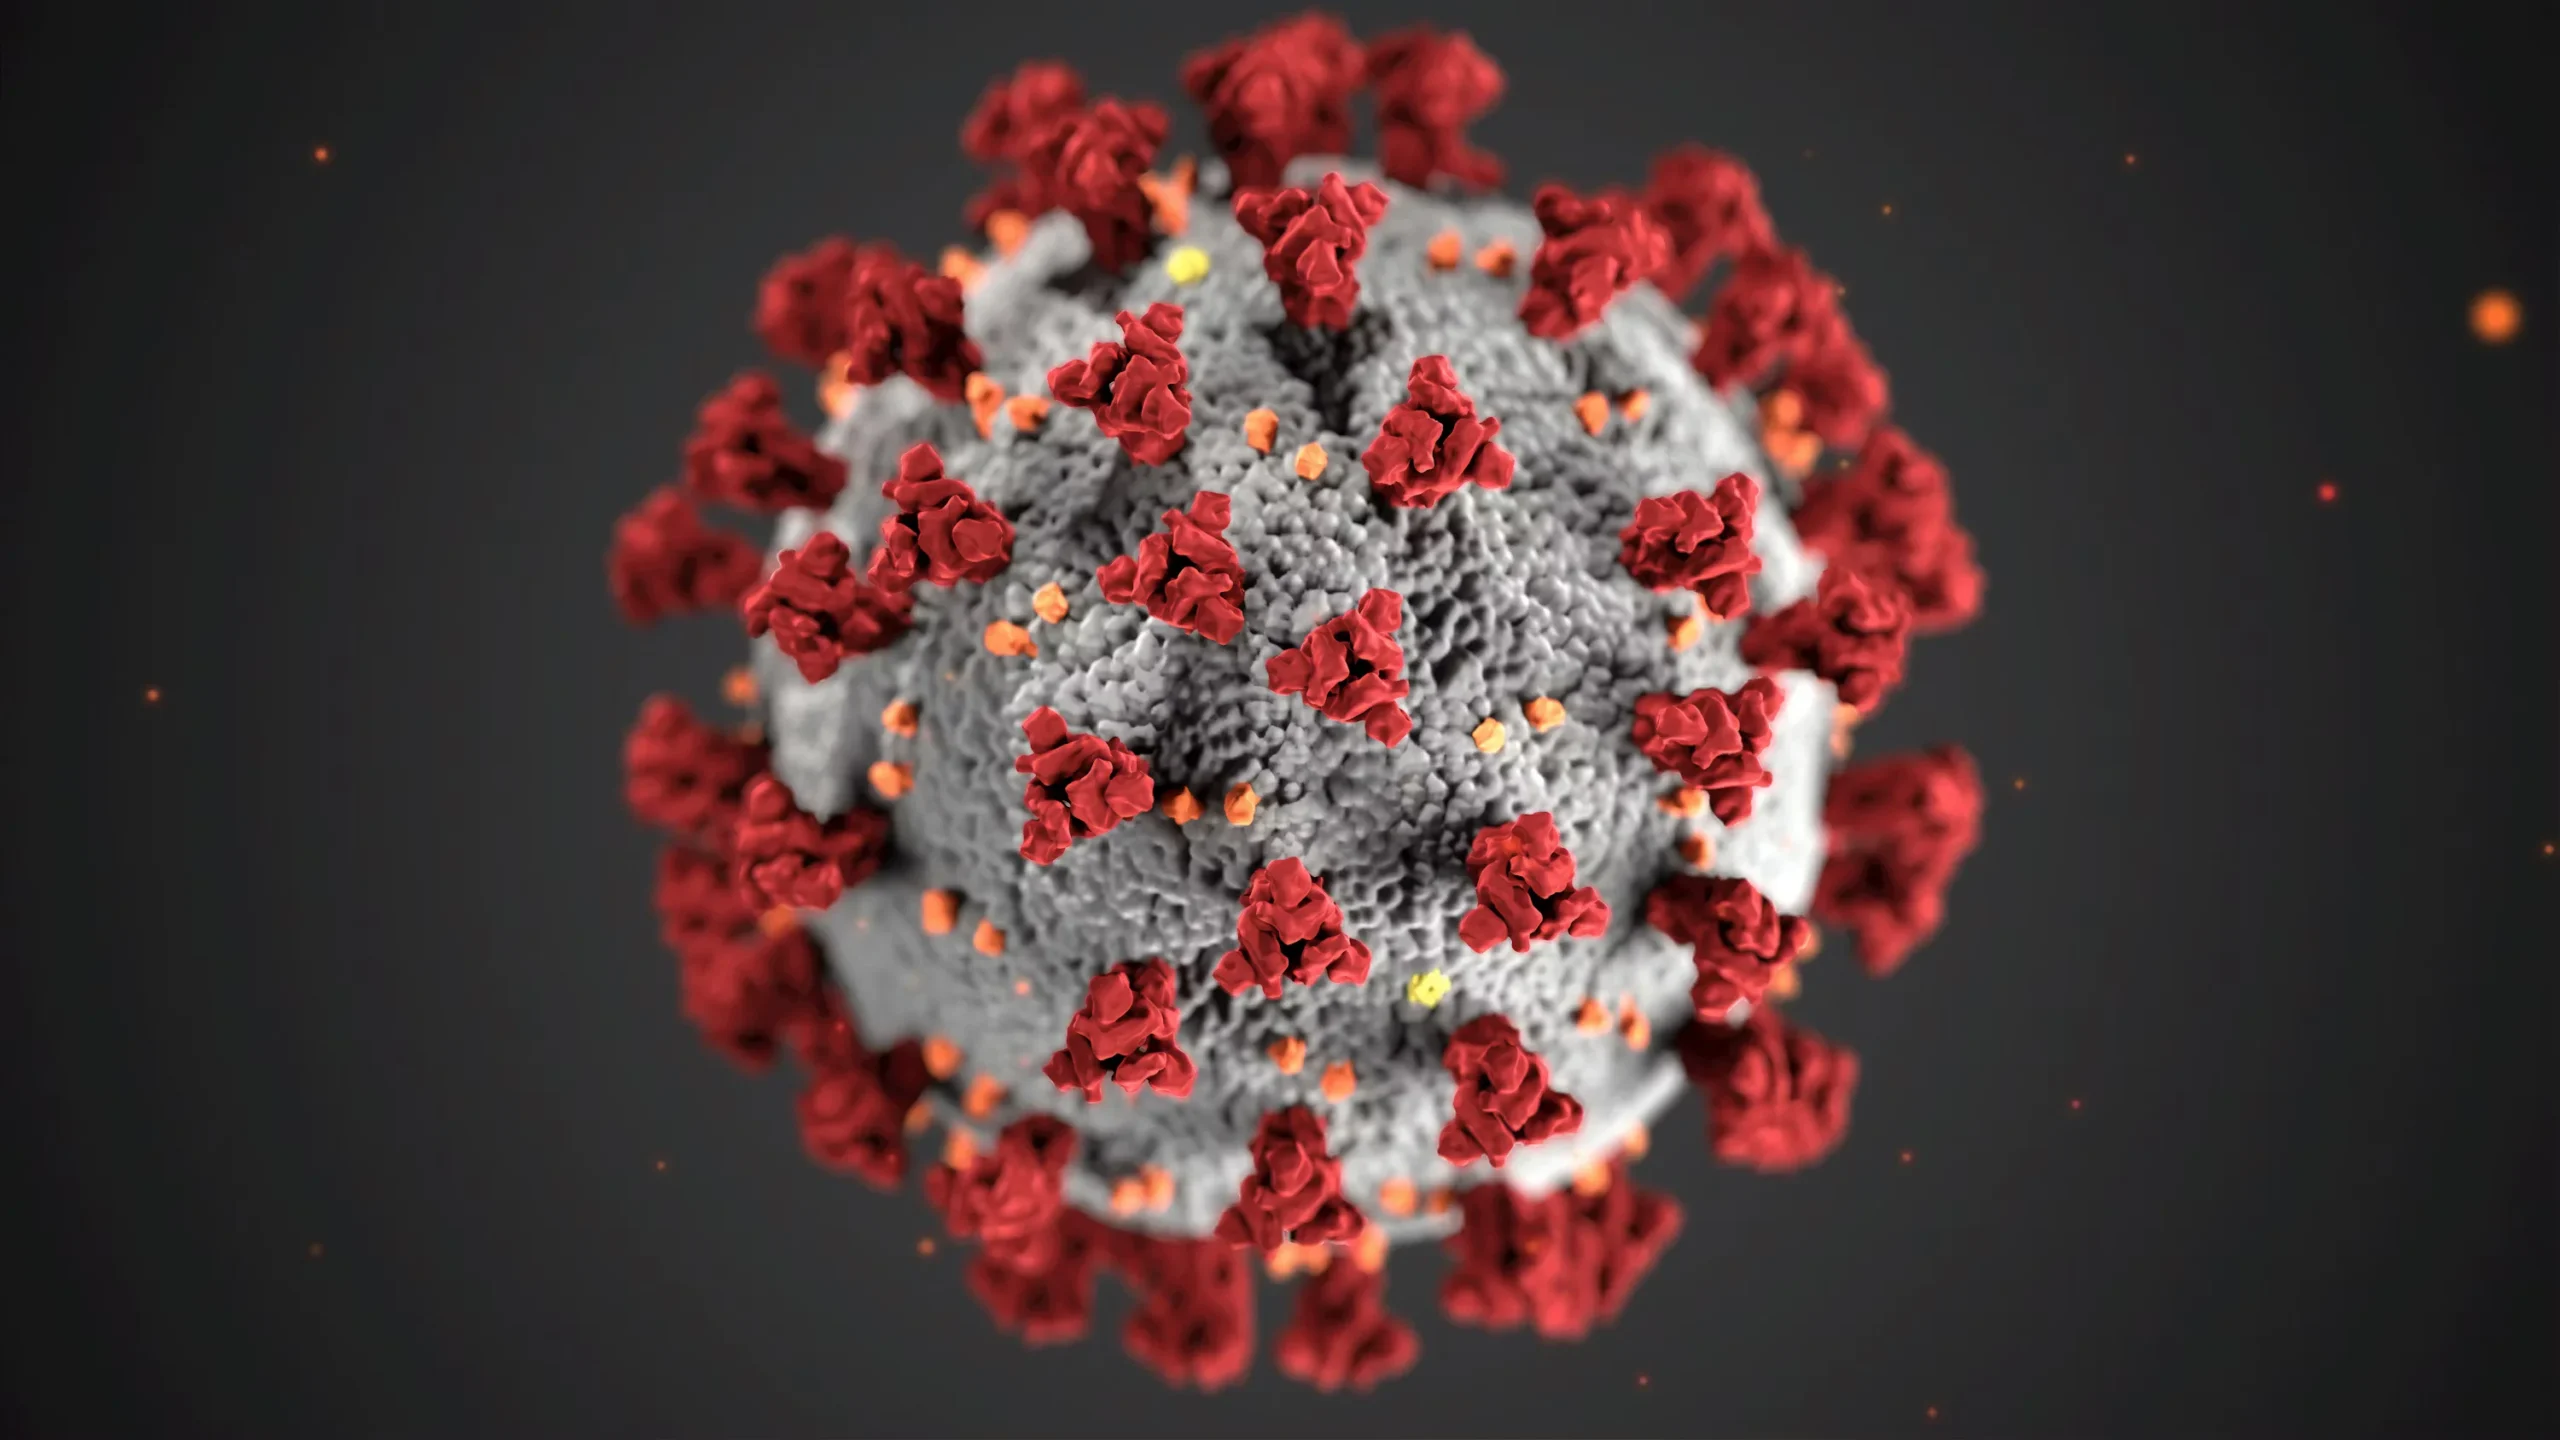

VírusCoronavírus

Grupo viral com reservatórios animais e potencial de transmissão humana.